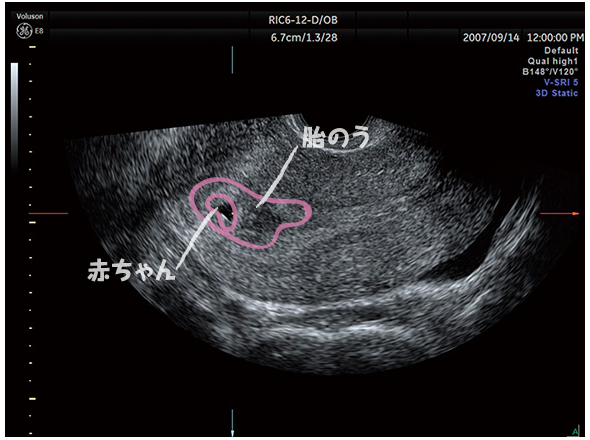

5 産科一般超音波検査 初期編 正常所見4 7週 日本産婦人科医会